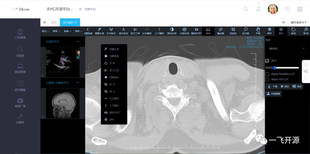

病历云 医疗平台 专攻医学软件方向 实验室 影像学 源码 下载

¥2020售1件